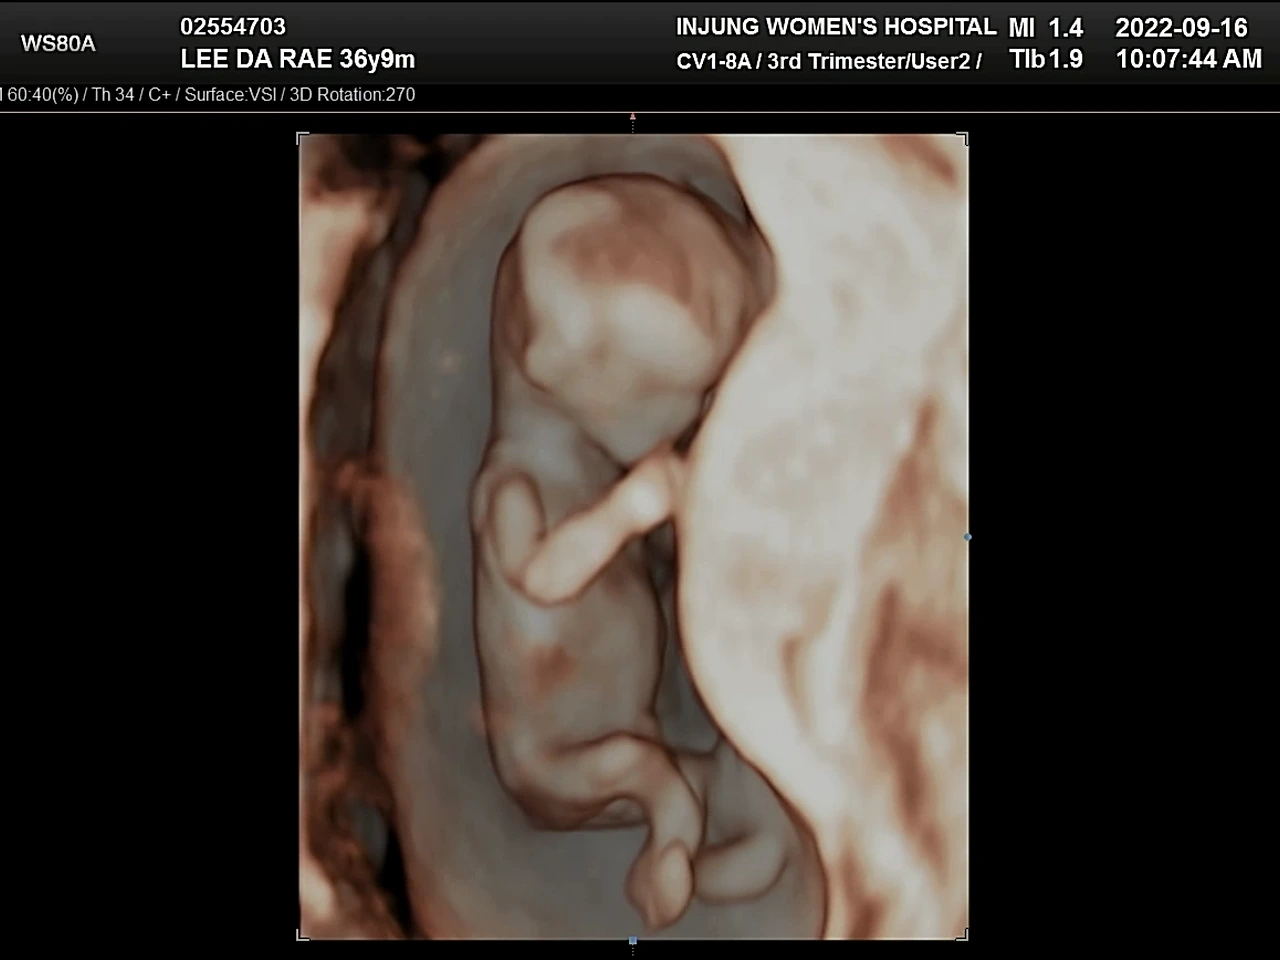

사람들이 안정기라고 부르는 12주에 들어섰다. 이때까지만 해도 병원에 가는 일이 무서웠다. 혹시나 아이가 잘못됐을까 싶은 마음이 컸기 때문이다. 제일 떨리는 순간은 초음파 화면이 흔들리면서 뱃속의 아이를 찾아 헤매다가 무언가 선명하게 보일 때. 이번엔 잘 모르는 내가 봐도 아이가 지난번보다 자라 있는 것 같아서 마음이 놓였다. 그다음 의사 선생님의 “아이가 많이 컸네요.”와 같은 멘트가 이어지고 심장소리를 들었다. 처음 아이의 심장소리를 들을 때보다 이때 들은 심장소리가 더 감동적이었다. 정밀초음파를 끝내고 1차 기형아 검사를 받으러 이동하는 길. 엘리베이터에서 나도 모르게 눈물이 났다. 유산의 두려움에서 어느 정도 벗어났기 때문만은 아니었다. 고작 12주인데, 아이에 대한 내 마음이 너무나 커져버렸다.